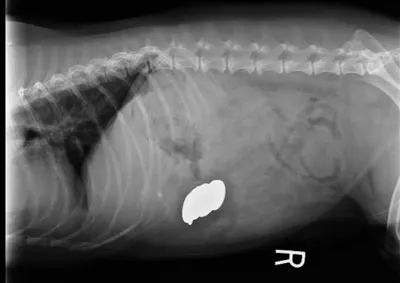

A complete blood count revealed marked neutrophilic leukocytosis with a moderate regenerative left shift, including rare metamyelocytes, toxic change, and monocytosis. Other laboratory findings included a hematocrit of 9%, mild macrocytosis, normal mean corpuscular hemoglobin concentration, increased nucleated red blood cells, and normal platelet count. A review of the blood film revealed 50% to 75% Heinz bodies, numerous spherocytes, and red blood cell ghosts (Figure 1).

A. Normal canine red blood cells; B. large Heinz body (arrow); C. spherocyte (note the absence of central pallor compared with normal red blood cells); D. ghost cell with retained Heinz body (arrow)